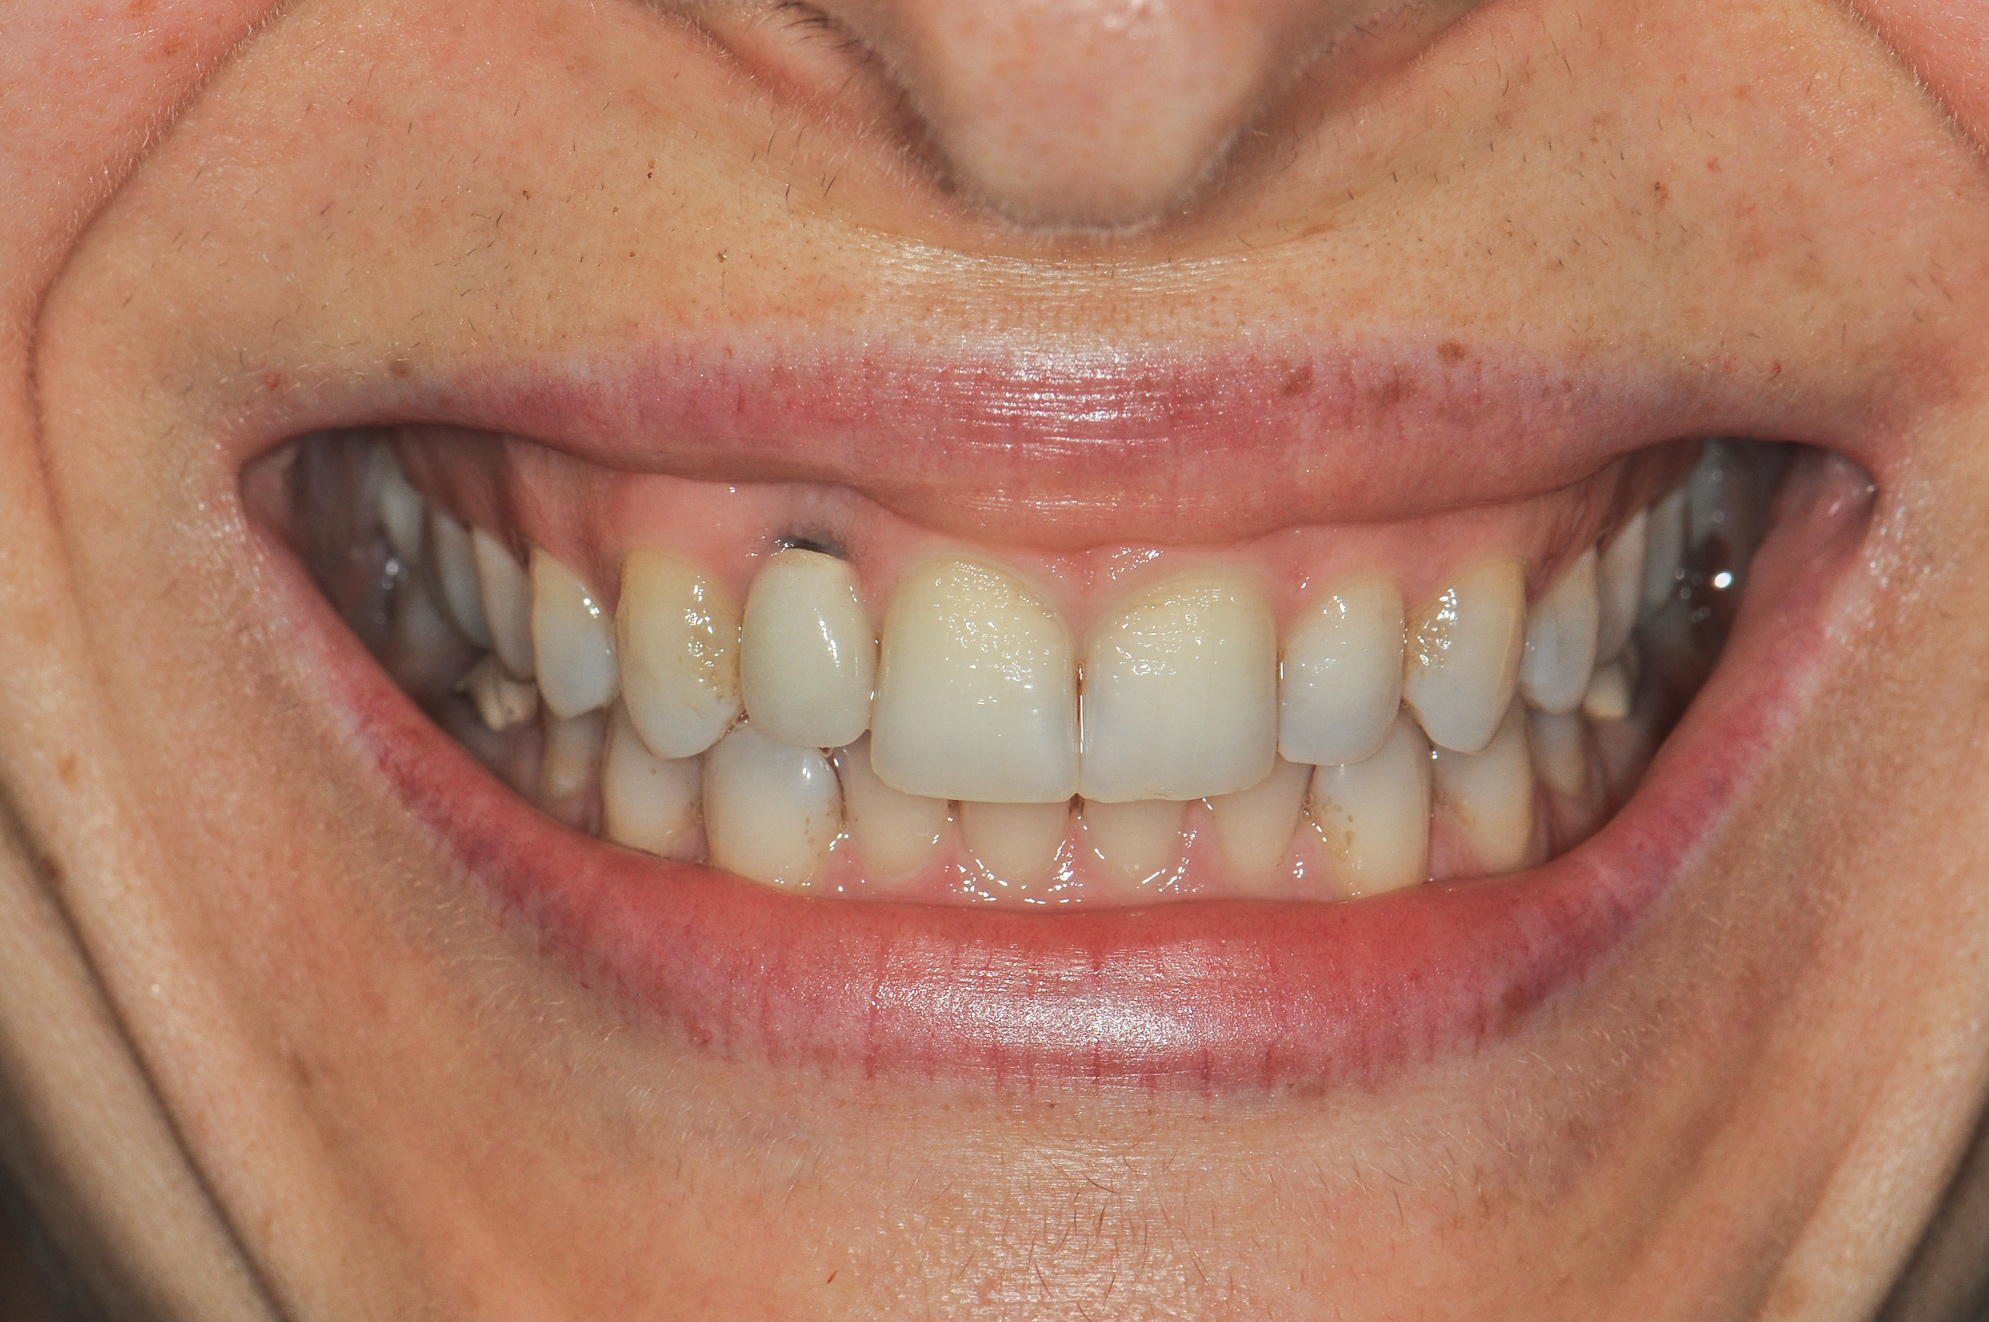

Figure 8 shows the provisionalization of No. 8 at 6 weeks postoperatively and a screw-retained provisional restoration on No. 9 to develop the subgingival transitional zone (key Nos. 8 through 10). The transitional zone will be duplicated using the custom impression coping technique. Figure 9 and Figure 10 depict the completed crowns at 5 years; implant No. 9 was screw-retained (key No. 10). In Figure 10 note the convex contours facial to implant No. 9 that are attributed to the connective tissue grafting as part of the surgical protocol creating biotype conversion from a thick to a thicker biotype. Figure 11 through Figure 13 show 5-year postoperative patient smile, periapical x-ray, and CBCT, respectively.

Fig 10. Completed crowns at 5 years, angled view. Note the convex contours facial to implant No. 9 attributed to the connective tissue grafting.

Figure 10